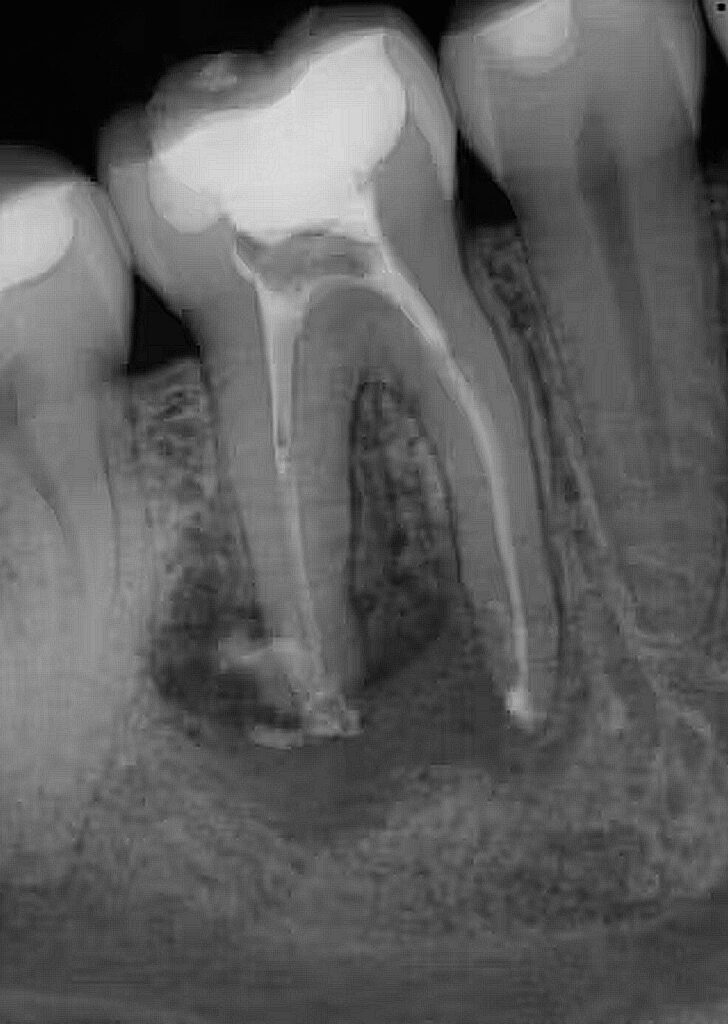

- Periodontitis (Advanced Gum Disease): This condition affects the underlying bone. If it progresses, teeth become loose and cause swelling. Unlike a cavity that usually affects one tooth, gum disease often impacts the whole mouth. We use 3D CBCT scans to evaluate every tooth. If the situation isn’t clear, we always attempt a “saving protocol” (such as deep cleaning) and monitor the results before moving toward an irreversible extraction.

- Failed Root Canals: Root canals have a success rate over 90%. However, if a re-treatment or surgical intervention fails, extraction is the final step to eliminate infection. (Rao S et al. (May 10, 2023) Incidence of Endodontic Failure Cases in the Department of Conservative Dentistry and Endodontics, DY Patil School of Dentistry, Navi Mumbai. Cureus 15(5): e38841. doi:10.7759/cureus.38841)

Standard 2D X-rays can hide curved roots or extra canals. At Finesse Dentistry, we use 3D CBCT Scans to see your tooth from every angle before we even touch an instrument. This technology allows us to:

- Evaluate every tooth in 360 degrees to see what can be saved versus what is truly beyond repair.

- Plan the exact path of removal and protect essential anatomy like nerves and sinuses.

- Section molar roots into smaller parts for a quicker, less traumatic “divide and conquer” exit.